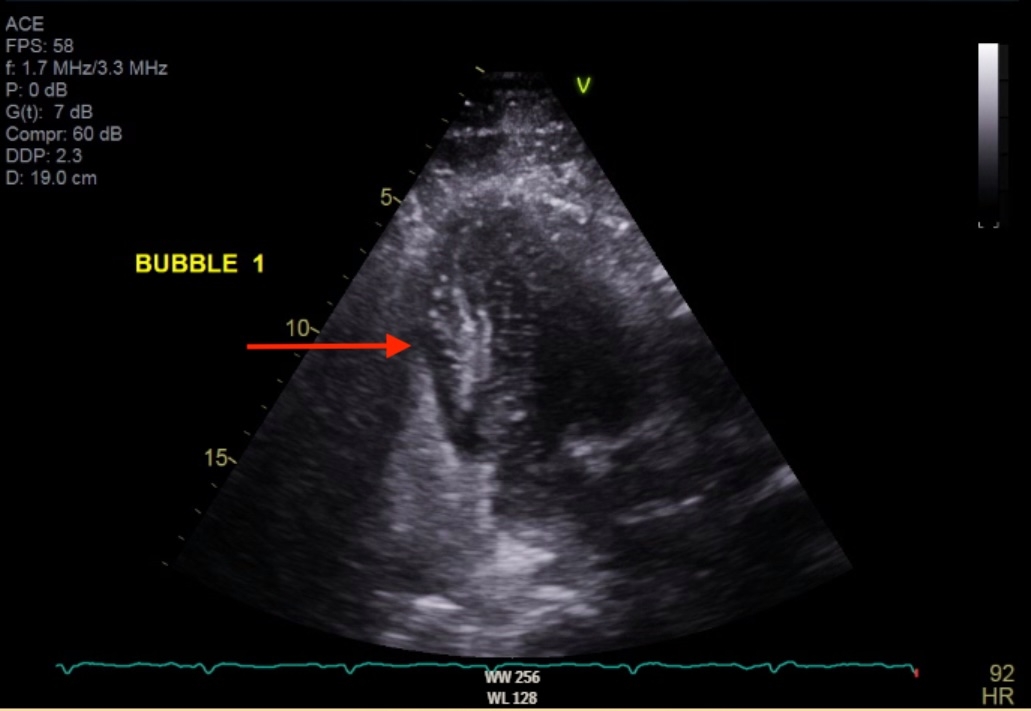

CT angiography revealed bilateral pulmonary emboli (PE) with right heart strain. Emergent coronary angiography showed occlusion of the left circumflex artery, which was successfully stented. Pulmonary thrombectomy was performed the following morning with effective clot extraction. Despite aggressive management, the patient developed progressive renal and hepatic failure with worsening lactic acidosis. Abdominal CT revealed extensive bowel ischemia due to acute mesenteric embolism. Transthoracic echocardiography with bubble study confirmed the presence of a patent foramen ovale with right-to-left shunting, consistent with paradoxical embolism.